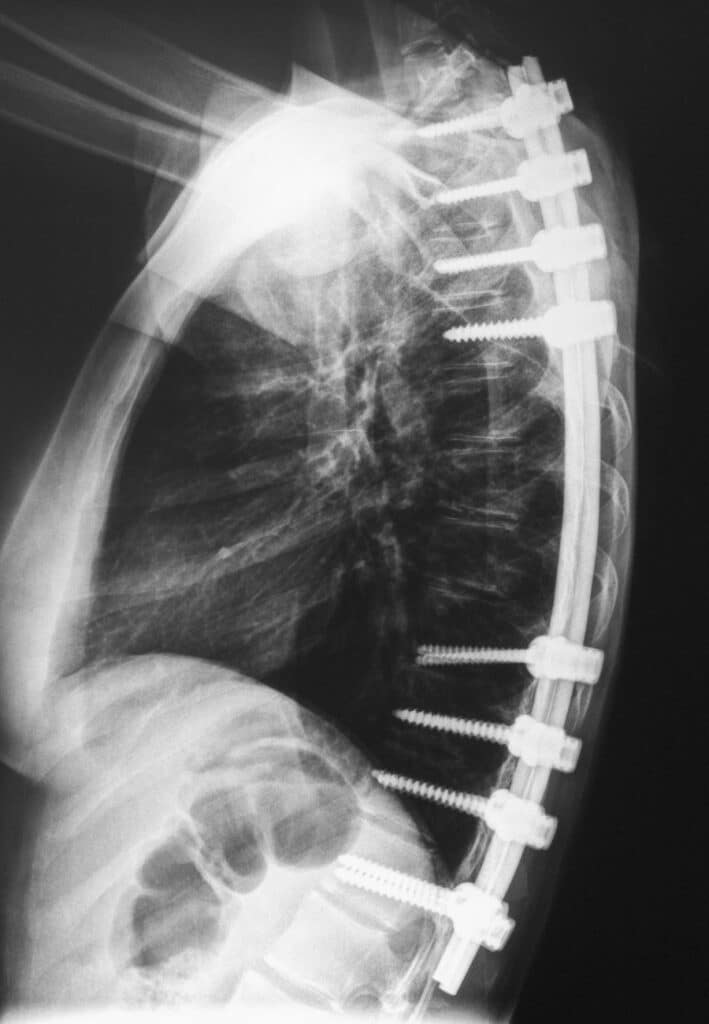

Types of Orthopedic Implants